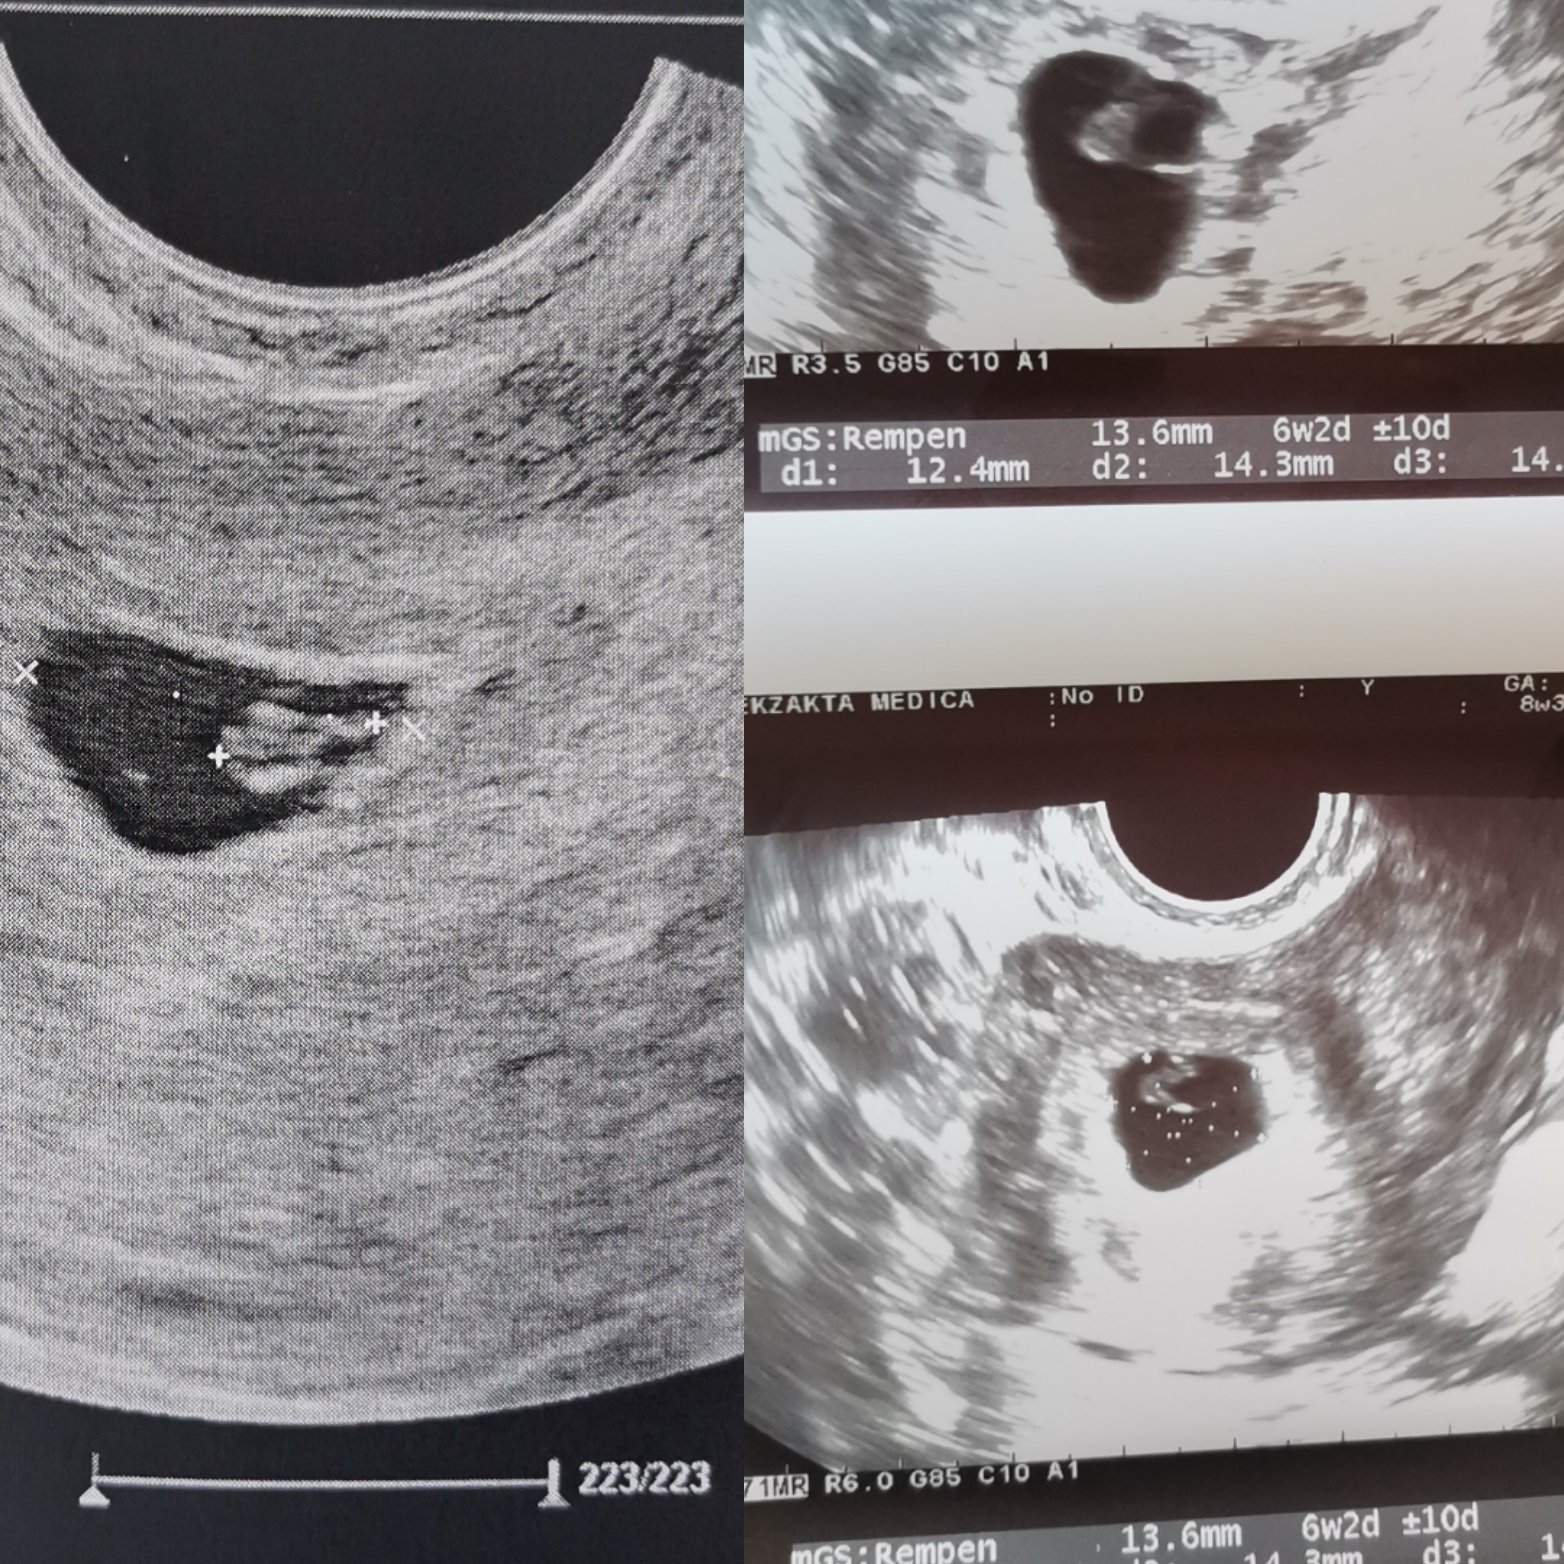

Не знам, при мен става все по-тъпо. Мина прегледа при другата докторка, ама ехографа и много зле, общо взето каза, че е 2 седмици назад, по принцип е назад, но дали чак толкова не знам. Не съм и казвала, че съм ходила другаде, за да не е пристрастна в това, което вижда и Мери. Все повече губя надежда, но може би другият четвъртък ще се разбере със сигурност.. Качвам снимки на прегледа от понеделник и от днес, изкажете мнение... Снимката в ляво е от понеделник, отдясно е от днес

Karadzhova88 аз на твое място бих отишла в някоя клиника с много добра апаратура, на която всичко се вижда, за да ти кажат най-накрая какво точно се вижда. Според мен си е ембрионче. Не се тормози повече и отиди ако трябва и на още 5 места. А и искам да забележиш, че на снимката пише +- 10 дни. На моята последна снимка пише +-4дни. При мен 12.46мм пишеше, че отговаря на 7+4.

Караджова,аз не разбирам,това 1 см и нещо размера на ембриона ли е ? Явно не, защото пише,че отговаря на 6+2,което съответства на размер на ембриона ,той в шеста седмица е около 4-5 мм. И аз не знам какво да те посъветвам,отиди на още едно мнение, трябва да е отлична апаратура.